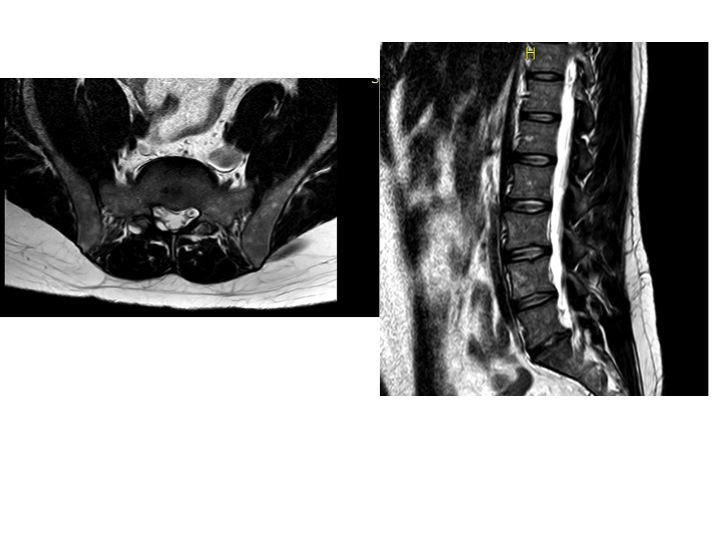

Allego immagine di RM

Commento file: Questa è una delle immagini di RM, spero possa rendere idea

Scrivo per sottoporvi una questione che mi sta facendo impazzire. Soffro di ernia discale dal 2009. Dopo innumerevoli visite specialistiche di tutti i tipi, finalmente il terzo neurochirurgo che consulto decide di operarmi. L''intervento è avvenuto circa un anno fa e devo dire che la qualità della vita mi è migliorata in quanto non sono più rimasto bloccato. Il problema è che non mi è mai scomparso il dolore cronico alla schiena e alle gambe, più precisamente un dolore localizzato tra polpacci e caviglie che a volte si estende sotto la pianta dei piedi. Il mio medico curante mi ha consigliato un reumatologo il quale mi ha prescritto una RM di controllo. Il referto parla di "ernia contenuta a livello l5s1". Poi il reumatologo ha però ritrattato asserendo che i dolori alle gambe non dipendono dall''ernia. Mi ha quindi consigliato di fare una elettromiografia.

Son tornato quindi dal neurochirurgo che mi ha operato, il quale afferma che quella che si vede non è un''ernia, ma un esito cicatriziale dovuto al disco che si riforma e viene intrappolato in una capsula, che il dolore alla schiena è dovuto ad una artrosi (di cui però il reumatologo consultando RX e RM non trova tracce) mentre il dolore alle gambe che provo non ha senso. mi ha detto che devo fare attività fisica come nuoto e corsa, nonostante non riesca a portarla a termine in quanto i dolori si acutizzano.

Mi chiedo se è vero che quella che è definita "ernia contenuta" (non ho studiato greco ma mi sembra un assurdo concettuale considerando l''etimologia della parola) possa essere un esito cicatriziale come afferma il mio neurochirurgo? Io speravo (vanamente) di potermi operare una seconda volta visto che in passato ho provato di tutto (farmaci, integratori, plantari, nuoto, fisioterapia e via dicendo) senza ottenere risultati. Considerando che non posso più consultare medici, come mi posso orientare? Se il deltacortene non dovesse fare effetto, potrei abbinarlo/sostituirlo con altro)? Esistono farmaci che posso prendere a vita per alleviare il dolore?